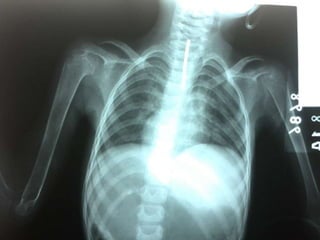

 1er semestre: En el cráneo

 2ndo semestre: Tórax

 Rosario Raquítico

 Hendidura De Harrison (El diafragma

tira de las costillas ablandadas durante

la inspiración)

Radiología

 Los cambios raquíticos se visualizan

con mayor facilidad en los Rayos X

posteroanteriores de muñeca.

 Disminución de la opacidad de las

metafisis. (imagen de doble contorno)

con una cortical que apenas destaca.

 (Nelson) metafisis de aspecto

deshilachado